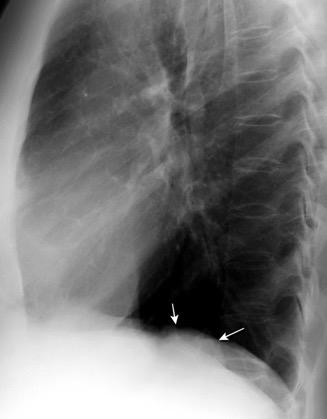

Diafragma “colgante” (“dangling sign”)

(“Dangling sign”)

TC. Mejor con multicorte. (reconstrucciones).

Asociación: Aire en pared.

Fracturas costal .Rotura esplénica. Neumoperitoneo.

Diafragma discontinúo Herniación de la grasa omental

Desser TS et al.The dangling diaphragm sign: sensitivity and comparison with existing CT signs of blunt traumatic diaphragmatic rupture. Emerg Radiol 2010